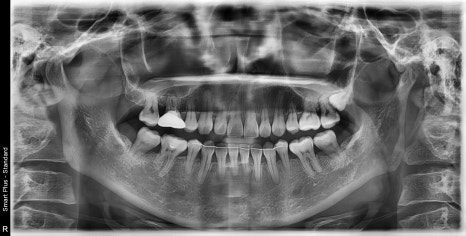

| 발치 전 | 발치 후 |